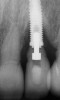

Some amount of microleakage can be expected with any current implant-abutment interface.23,24 External hexagon implants have been found to fail to prevent microleakage.23 Figure 3 and Figure 4 depict an external hexagon implant with an implant-abutment connection vulnerable to microleakage. This same study found internal hexagon implants with internal conical (Morse taper) connection to have the least amount of leakage. Zirconia abutments were found to have more microleakage than titanium abutments. As a result, this study recommended restricting the use of zirconia abutments to cases where esthetic demands are high.23

Fig 3. Clinical and radiographic views of an external hexagon implant restored using a zirconia abutment. The radiograph indicates an implant–abutment connection vulnerable to microleakage. Severe bone loss was due to peri-implantitis.

Figure 3

Fig 4. Clinical and radiographic views of an external hexagon implant restored using a zirconia abutment. The radiograph indicates an implant–abutment connection vulnerable to microleakage. Severe bone loss was due to peri-implantitis.

Figure 4